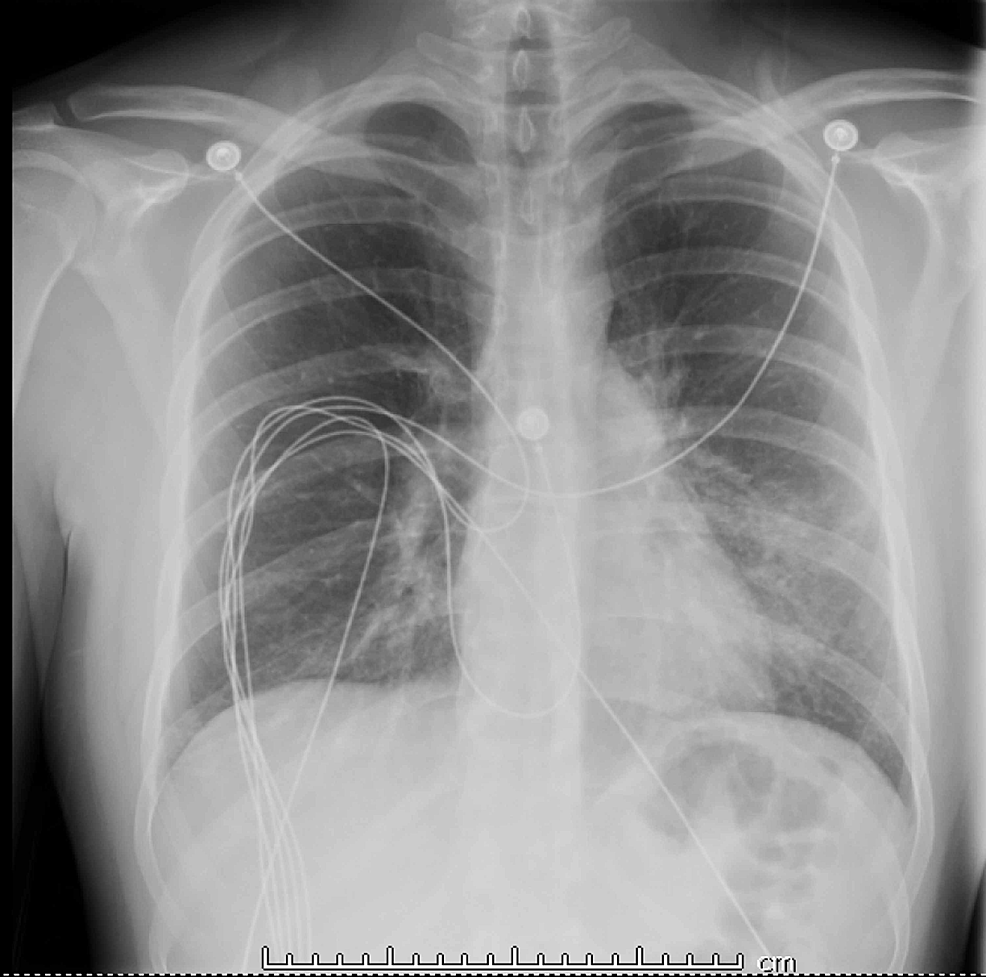

Vaping provokes lung disease in healthy individuals identified on CT

Vaping provokes lung disease in healthy individuals identified on CT Does A Chest Xray Show If You Vape The long term risks are unknown but. three criteria define evali: these include shortness of breath, fever and chills, cough, vomiting, diarrhea, headache, dizziness, rapid heartrate and chest pain. we identified four imaging patterns that correlated with pathological findings attributable to vaping, including. another study published in the new england journal of medicine identified that many. Does A Chest Xray Show If You Vape.